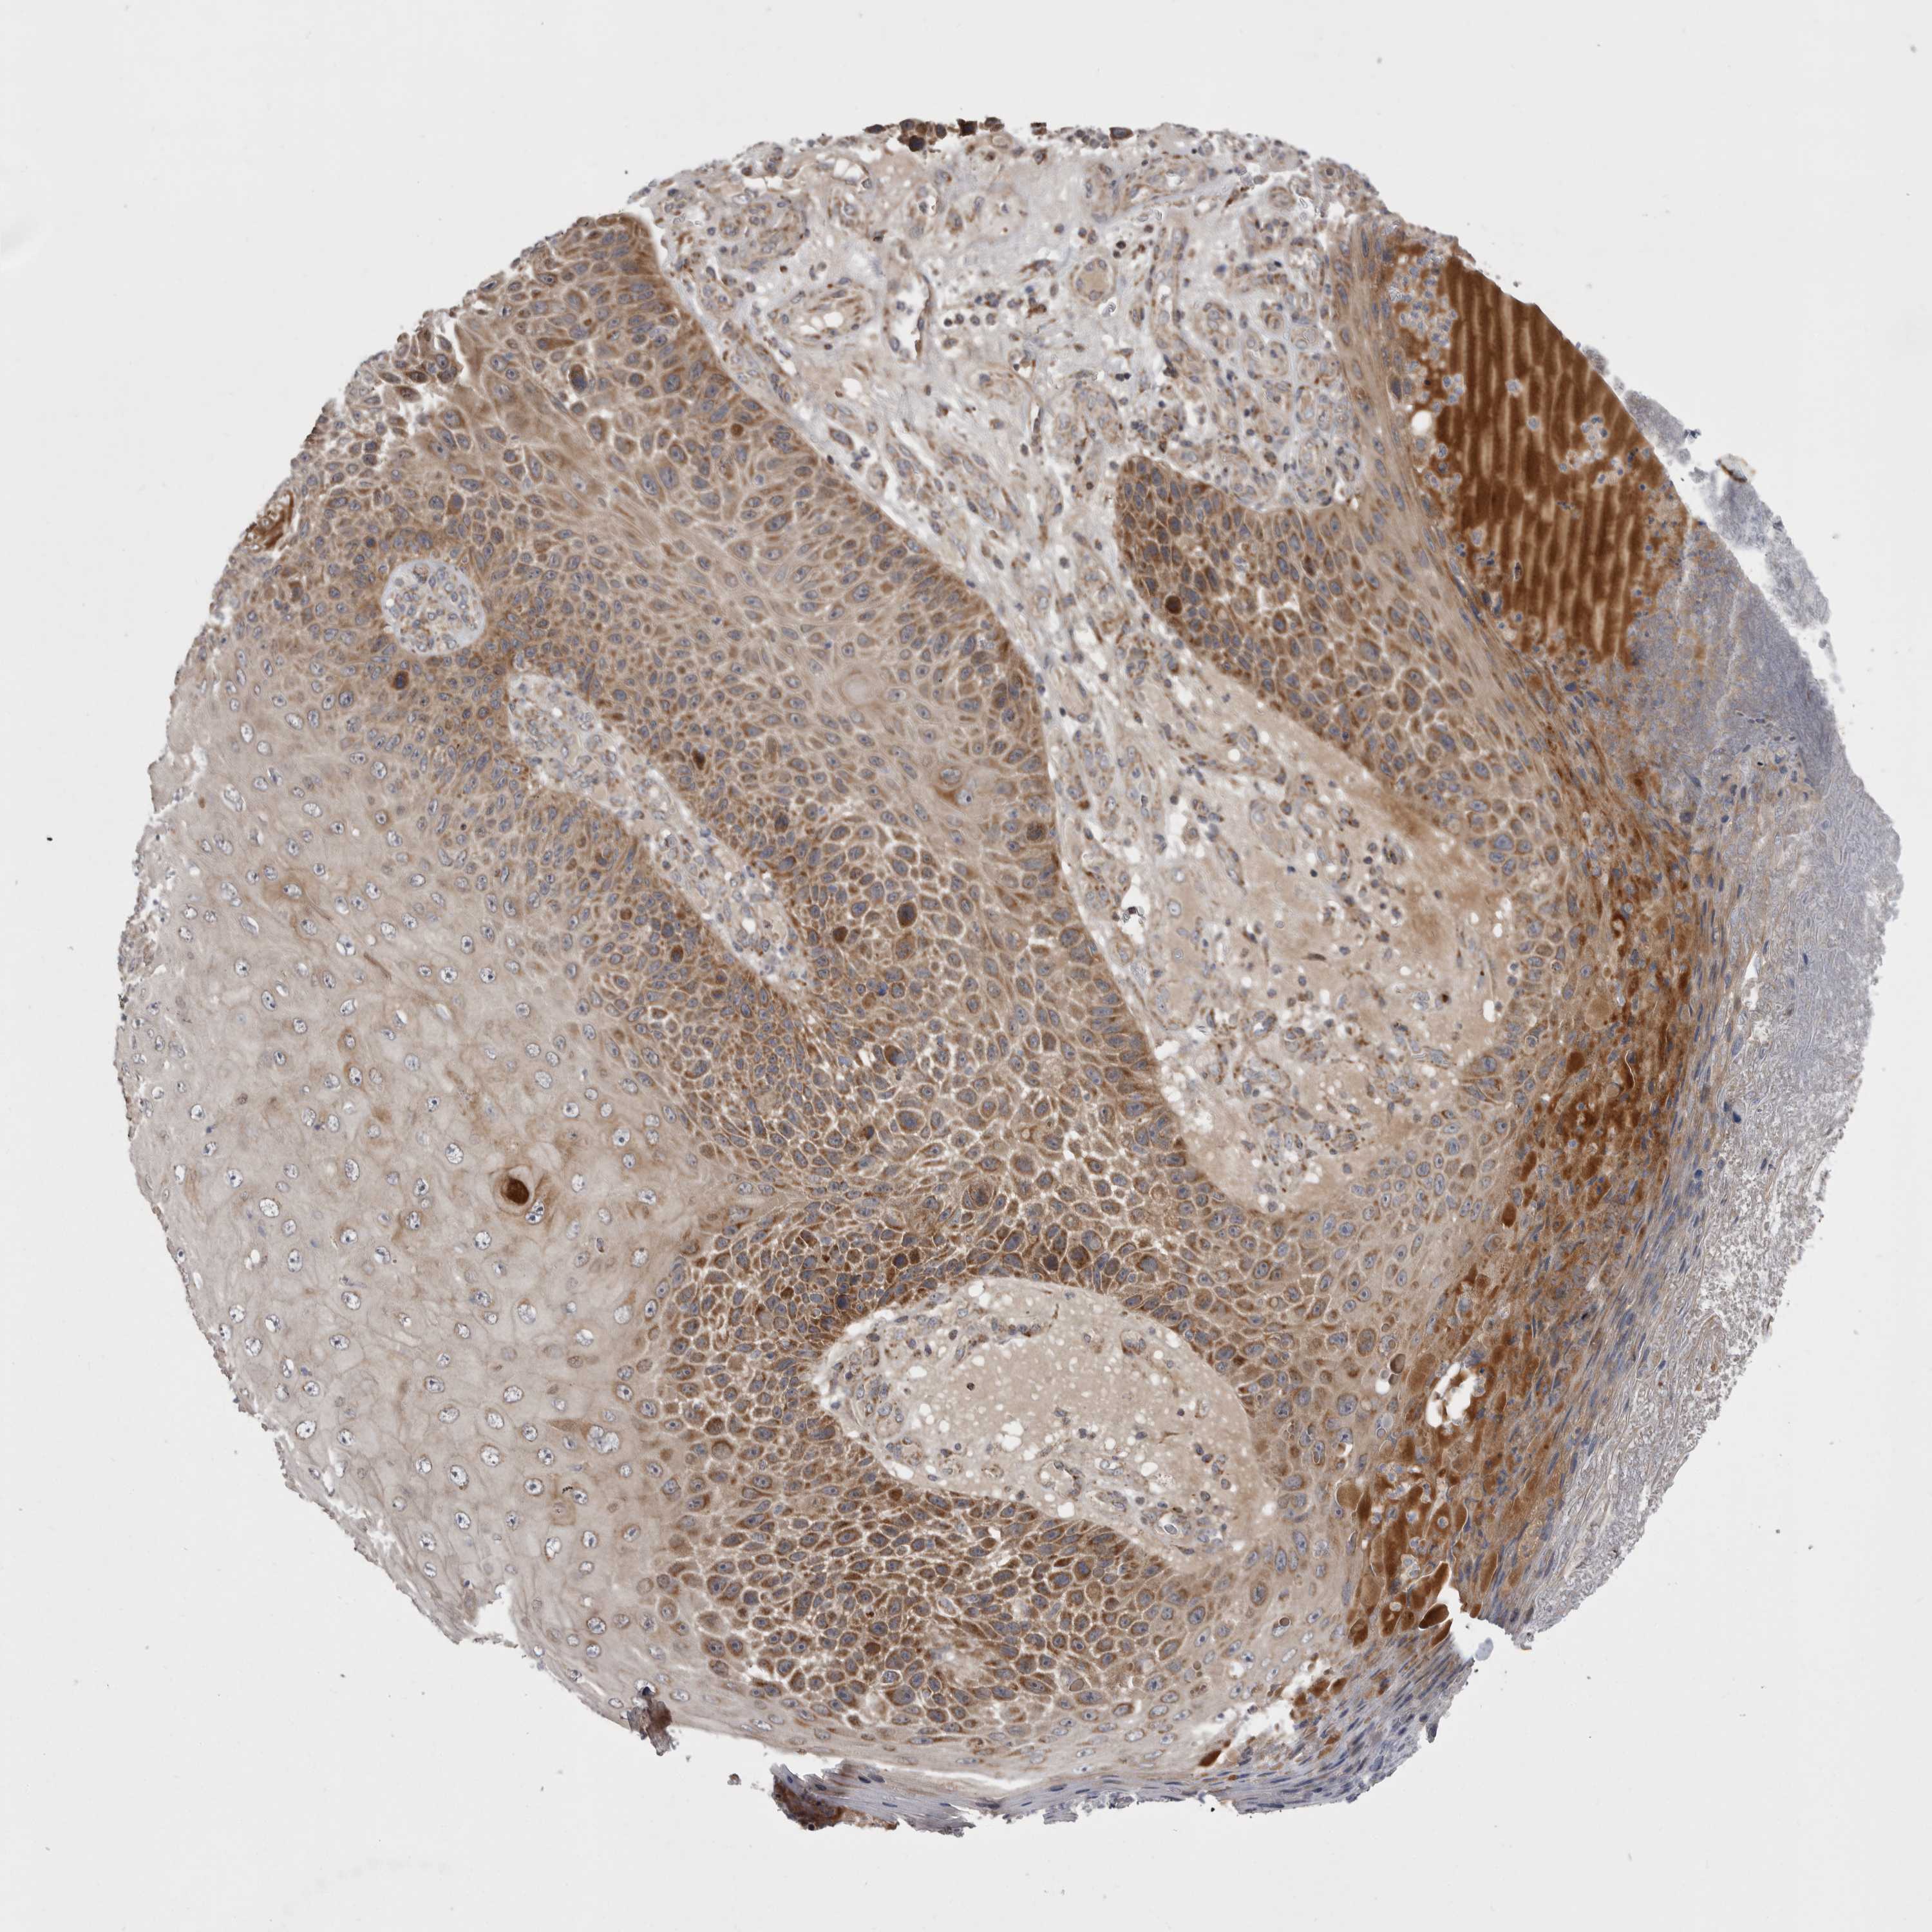

SKIN CANCER - Protein expressioni

A mouse-over function shows sample information and annotation data. Click on an image to view it in a full screen mode. Samples can be filtered based on level of antibody staining by selecting one or several of the following categories: high, medium, low and not detected. The assay and annotation is described here.

Each image is clickable and will lead to virtual microscopy that enables deeper exploration of all samples and also displays staining intensity scores, fraction scores and subcellular localization as well as patient and tissue information for each sample.

Antibody HPA027168

Squamous cell carcinoma, metastatic, NOS

Squamous cell carcinoma, NOS